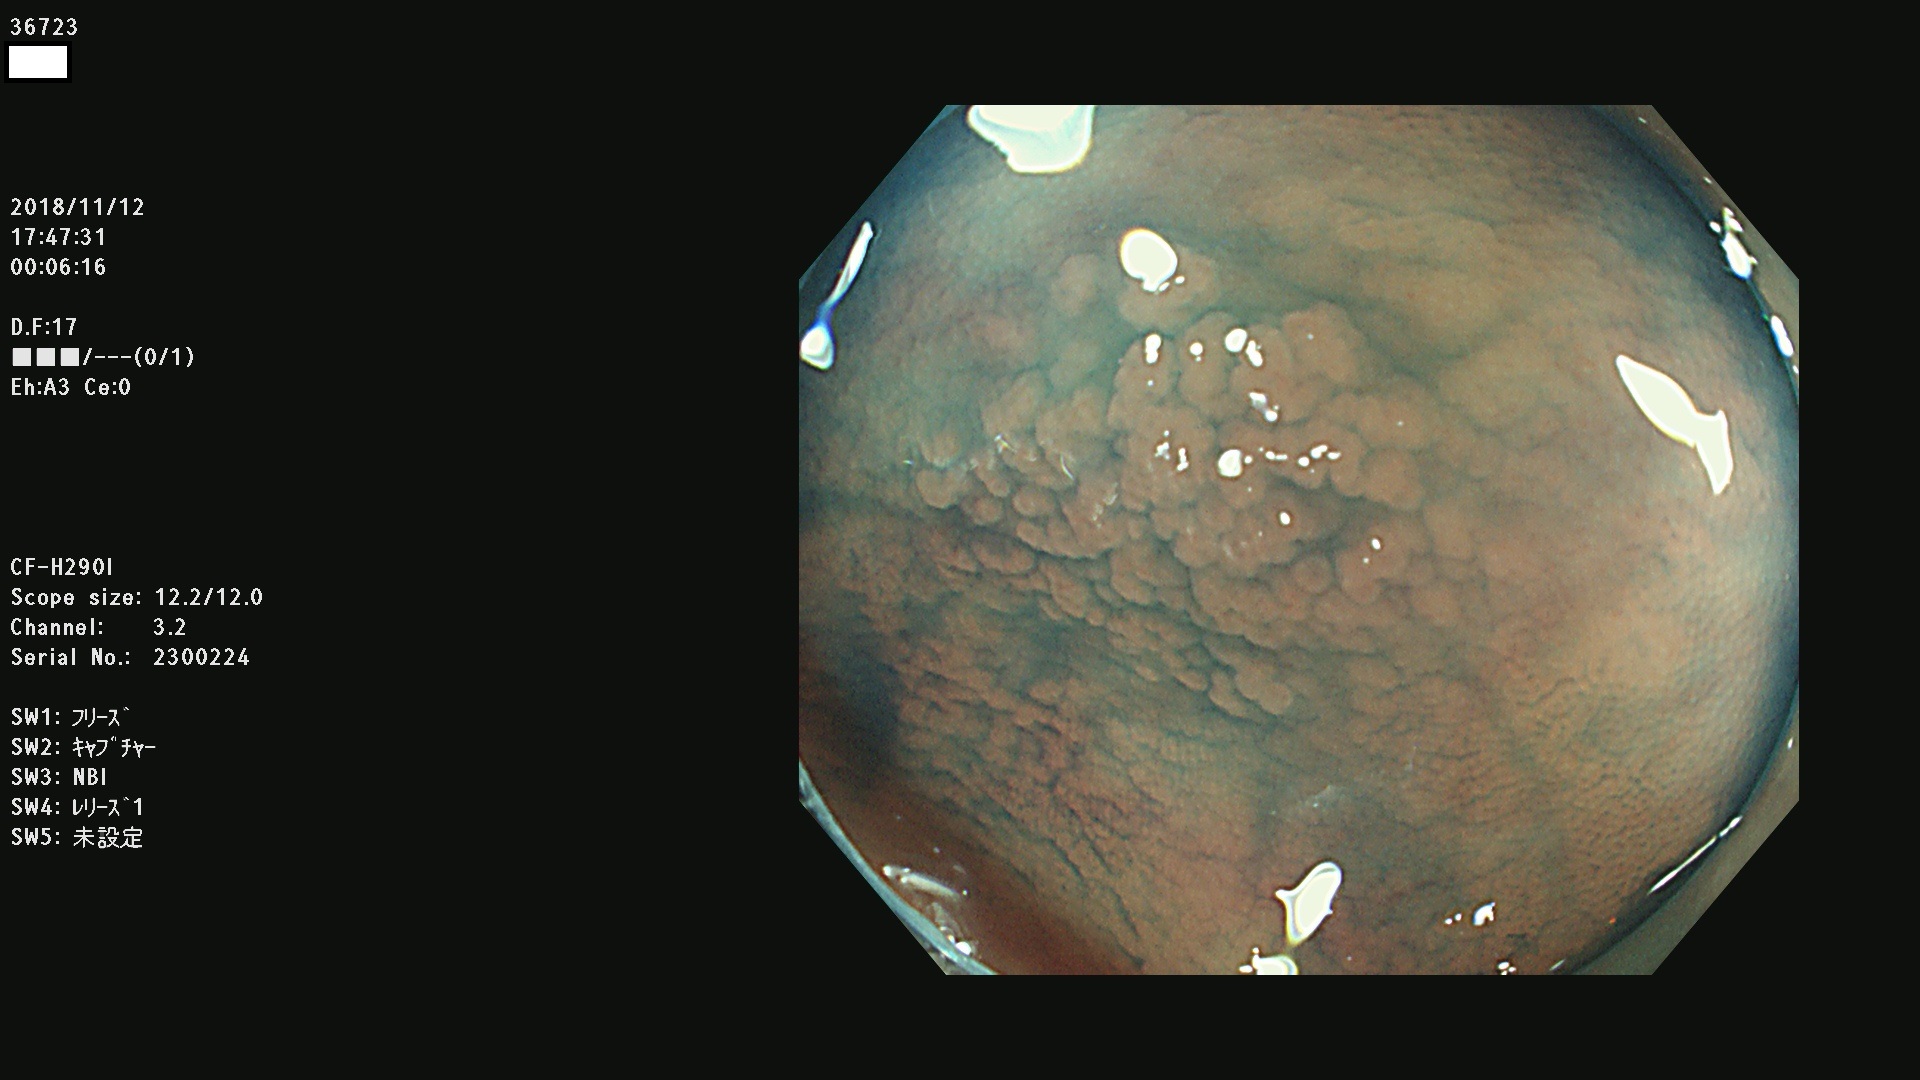

36700 36701 36702 36704 36705 36707 36708 36710 36712(SSAPのみ) 36714 36715 36716 36717 36718 36721 36723 36724 36730 36731 36732 36734 36735 36736 36738 36739 36742 36744 36745 36746 36749 36752(SSAPのみ) 36754 36756 36758 36759 36760 36731 36732 36734 36737 36738 36739 36771(SSAPのみ) 36772 36773 36774 36775 36776 36777 36780 36781 36783 36785 36786 36788 36790 36792 36794 36797 36798

発見困難で危険性の高い平坦型病変(上記100名より抽出)